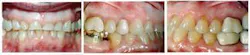

A 55-year-old female presented for restorative treatment of her anterior teeth (Figure 1). She had a history of bulimia during college, which resulted in extensive erosion of her maxillary anterior teeth. Her lower anterior teeth had super-erupted, leaving her with a reverse smile line. Upon clinical examination, we noted that she had good oral hygiene, extensive incisal tooth loss of all her anterior teeth, erosion at the cementoenamel junction, and a history of clenching/grinding. She reported that she had controlled the bulimia for years, and was seeking good esthetics and function.